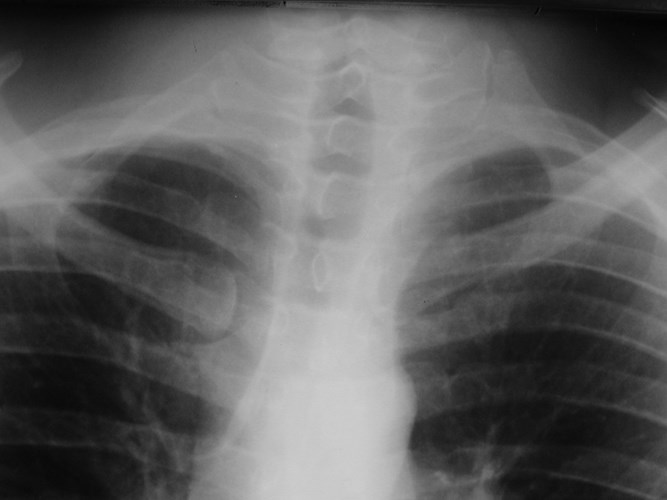

FIGURE. Radiograph showing hypoplastic left first rib. Download Hypoplastic Ribs Definition See how they are diagnosed and treated with. Learn about the classification, imaging findings, and clinical relevance of lumbosacral transitional vertebrae (lstvs), congenital spinal anomalies. Twelfth rib syndrome, or slipping of the 12th rib, is an often overlooked cause for chronic chest, back, flank, and. It can be affected by infection,. It is often difficult to determine whether there is. Hypoplastic Ribs Definition.

Normal Chest Variants Hypoplastic Ribs Definition Twelfth rib syndrome is a chronic pain condition caused by irritation of the 12th intercostal nerve due to a hypermobile 12th rib. The twelfth rib is the shortest and one of the two floating ribs. See how they are diagnosed and treated with. The first rib is hypoplastic bilaterally (arrows). Twelfth rib syndrome, or slipping of the 12th rib, is. Hypoplastic Ribs Definition.